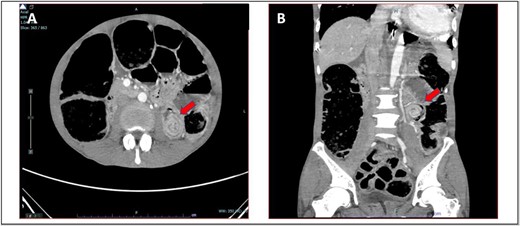

She was presented with an umbilical swelling for the past 1 week which had become painful for the past 2 days, associated with vomiting and unable to pass flatus and bowel motion. On examination, her vitals were normal. Per abdomen, there was 4 × 4 cm swelling at umbilicus with redness and skin changes. Plain abdominal radiograph showed dilated small bowel (Fig. 4A). Her blood parameters showed leukocytosis with white cell counts of 20, haemoglobin of 15, acute kidney injury with urea of 17, and creatinine of 154. Arterial blood gas was normal and no acidosis. The provisional diagnosis was strangulated paraumbilical hernia.

(A) Plain abdominal radiograph showed dilated small bowel (B) intraoperative finding of unhealthy sloughy small bowel segment in the hernia sac and pus was present.

We discussed with patient and her relative regarding the option of anaesthesia either local or general anaesthesia. They agreed and consented for local anaesthesia since it has the least complications and aware of conversion to general anaesthesia if the former method failed to work. We proceeded with the surgery under local anaesthesia and monitored sedation with the help of an anaesthesiologist. We did an infraumbilical transverse incision over the hernia and found small bowel ischemia within the hernia sac with pus (Fig. 4B). The hernia defect was 3 × 3 cm. Ten centimeters of segment small bowel was resected with primary side to side bowel anastomosis using linear stapler 75 mm. The hernia defect is primarily closed with nonabsorbable polypropylene suture. The skin was left open for wound dressing. She recovered slowly from surgery and was able to go home on Day 7 post-operation.